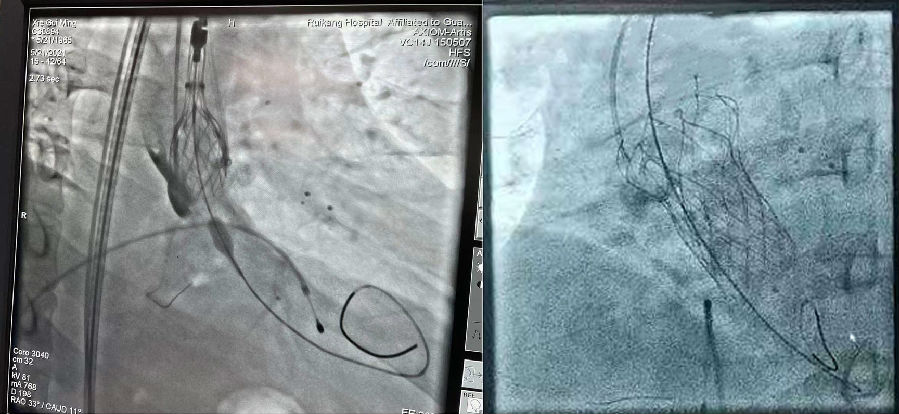

行经导管主动脉瓣置入术中

术中精准定位及释放,经主动脉造影显示贴位良好,无明显反流